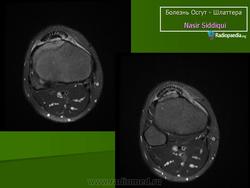

На рентгенограмме выявляются признаки фрагментации бугорка болылеберцовой кости.

На рентгенограмме отек мягких тканей, утолщение хряща, покрывающего бугристость спереди, фрагментация бугристости

В оценке рентгенологических признаков болезни Шлаттера необходимо учитывать большое число вариантов нормальной оссификации апофиза большеберцовой кости, разный ее характер справа и слева [Рейнберг С. А., 1964; Радулеску А., 1967]. Поэтому диагностику основывают на данных клиники (боль, припухлость) и несоответствии между значительным выбуханием хряща бугристости и меньшей ее величиной на рентгенограмме.